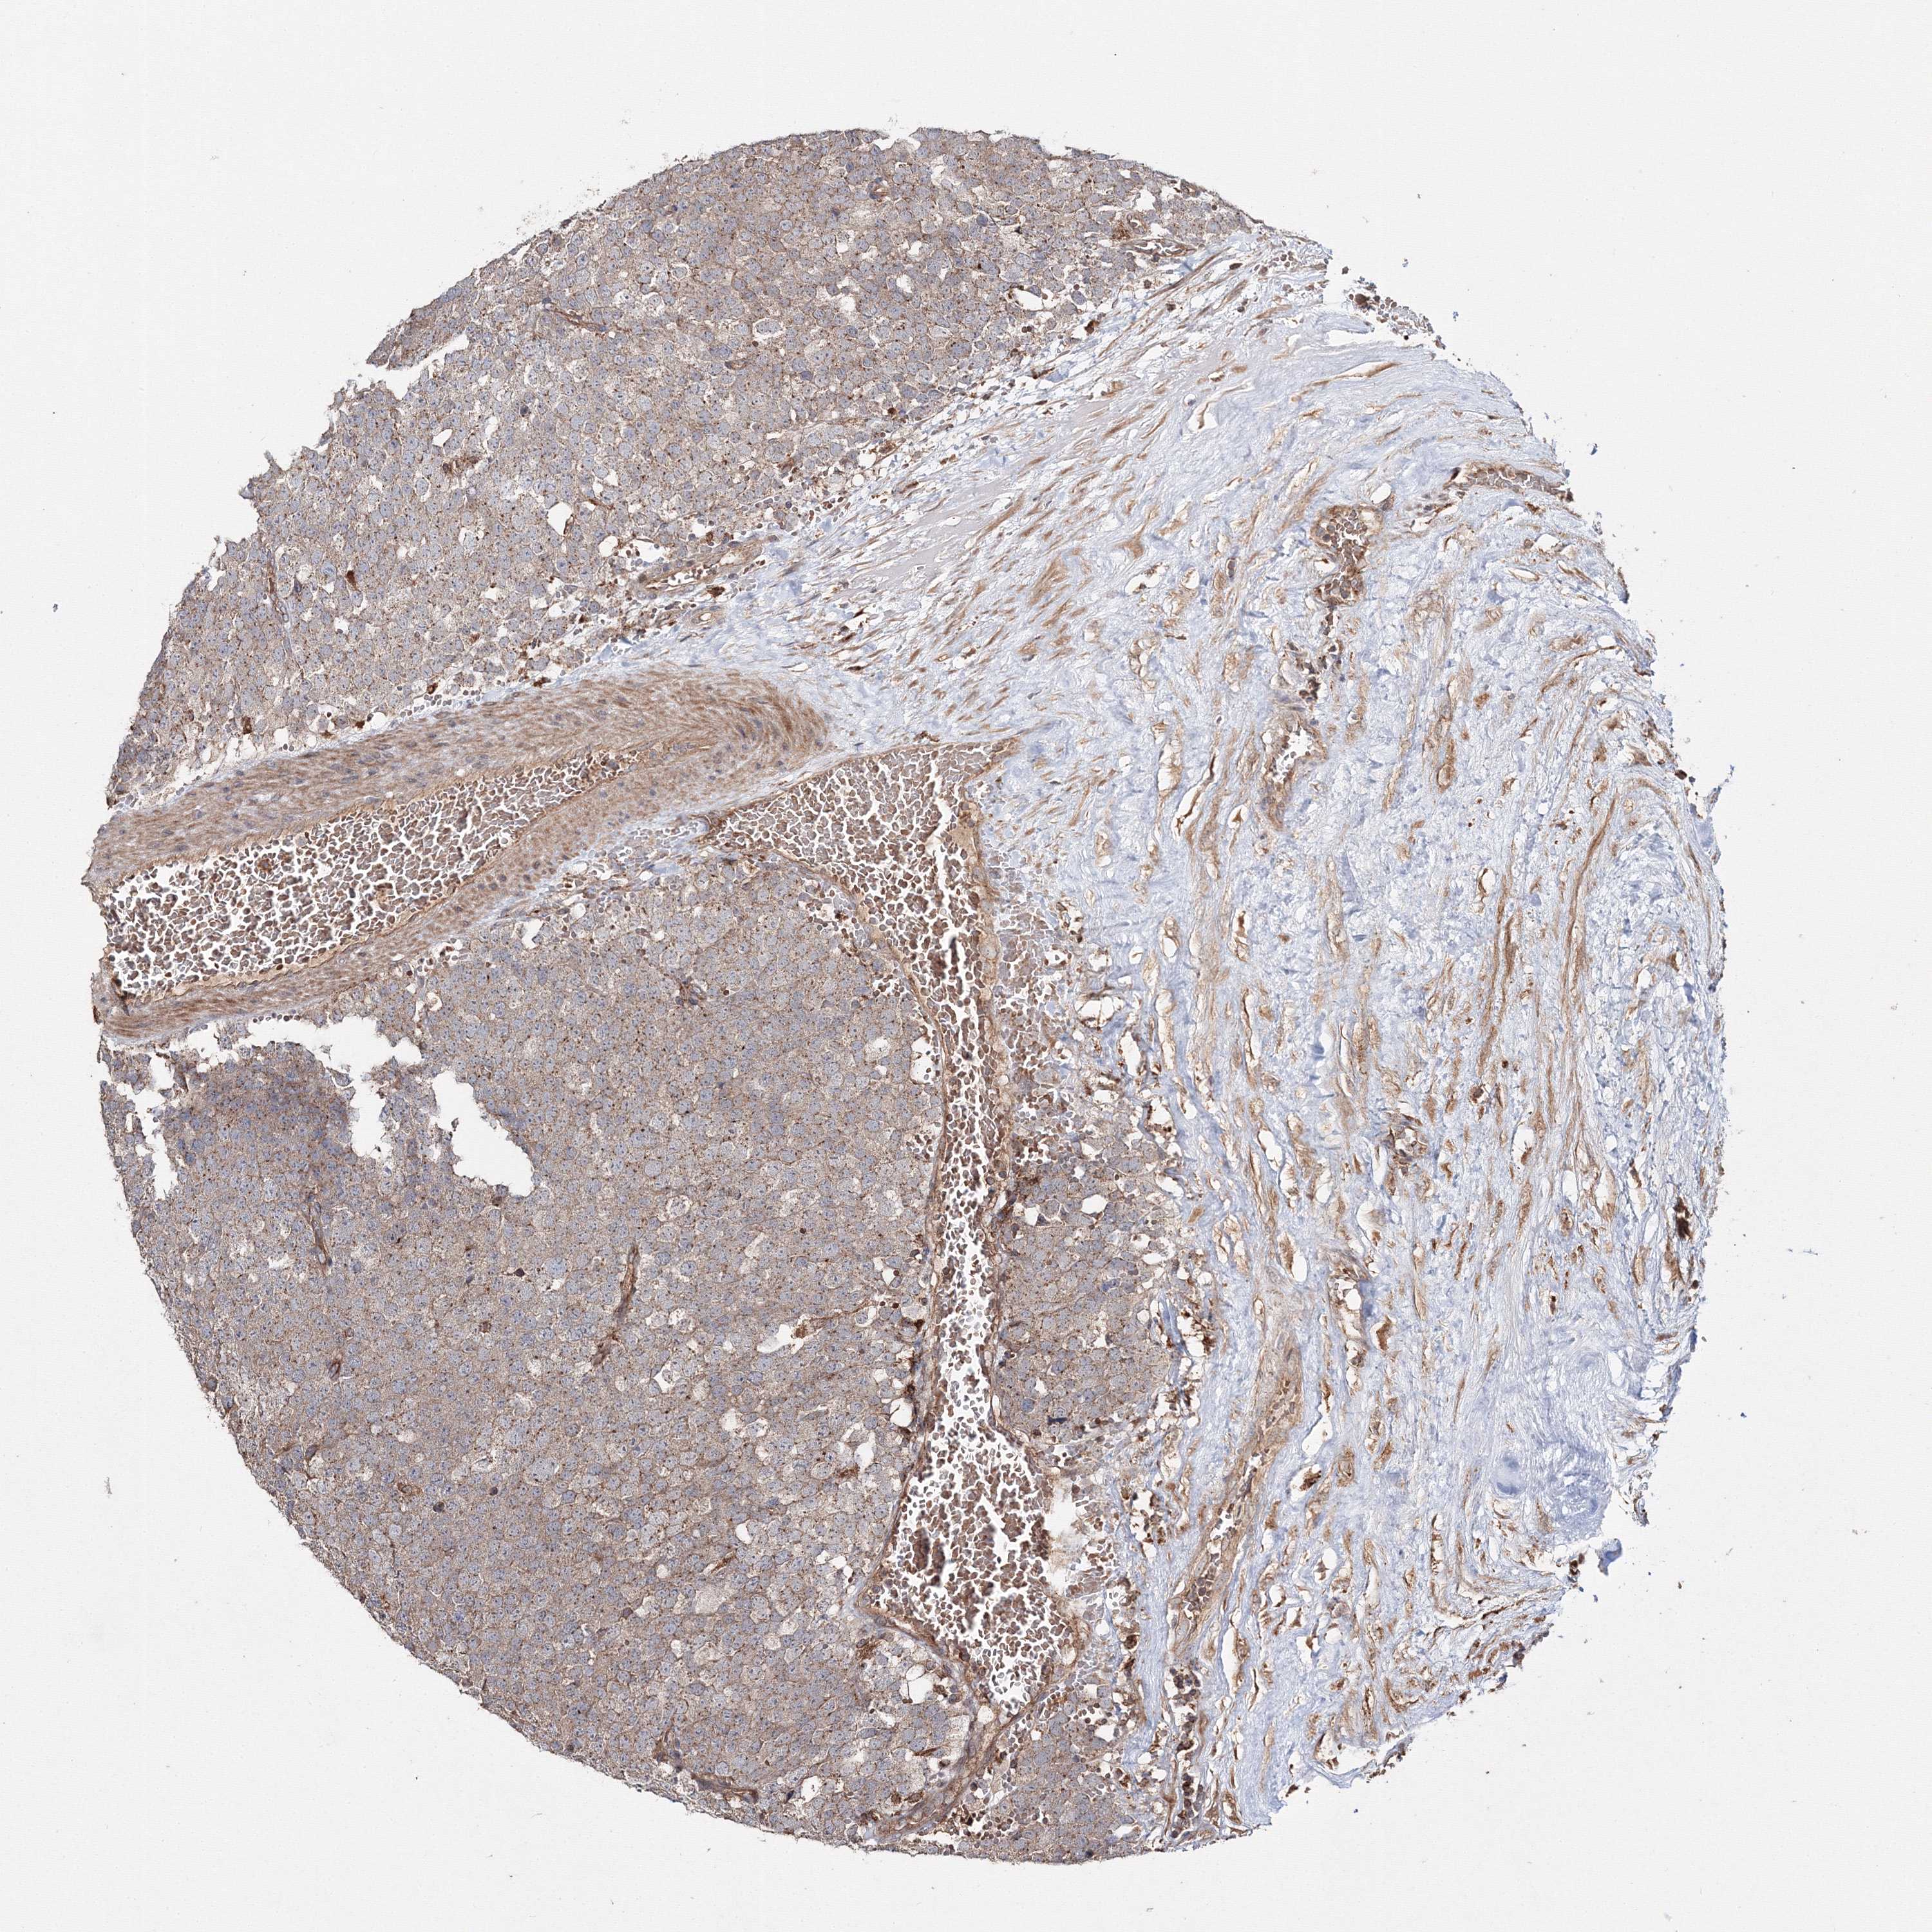

TESTIS CANCER - Protein expressioni

A mouse-over function shows sample information and annotation data. Click on an image to view it in a full screen mode. Samples can be filtered based on level of antibody staining by selecting one or several of the following categories: high, medium, low and not detected. The assay and annotation is described here.

Note that samples used for immunohistochemistry by the Human Protein Atlas do not correspond to samples in the TCGA dataset.

Antibody stainingi

Antibody staining in the annotated cell types in the current human tissue is reported as not detected, low, medium, or high, based on conventional immunohistochemistry profiling in selected tissues. This score is based on the combination of the staining intensity and fraction of stained cells.

Each image is clickable and will lead to virtual microscopy that enables deeper exploration of all samples and also displays staining intensity scores, fraction scores and subcellular localization as well as patient and tissue information for each sample.

Antibody HPA037525

Antibody HPA037526

Staining

High

Medium

Low

Not detected

Intensity

Strong

Moderate

Weak

Negative

Quantity

>75%

75%-25%

<25%

None

Location

Nuclear

Cytoplasmic/membranous

Cytoplasmic/membranous,nuclear

Carcinoma, Embryonal, NOS

Seminoma, NOS